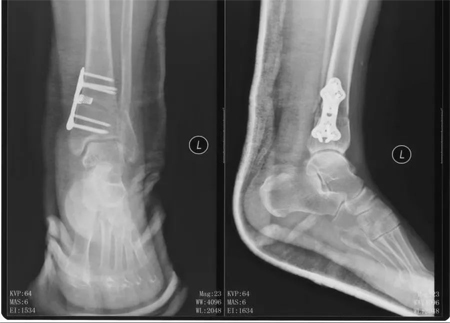

本次手术前,患者双侧踝关节的x片,可见右侧踝关节截骨术后改变,矫正角度良好,左侧为早期轻度内翻型踝关节炎。

术后第二天,患者踝关节的X片,可见截骨矫形满意,内固定位置满意可靠。